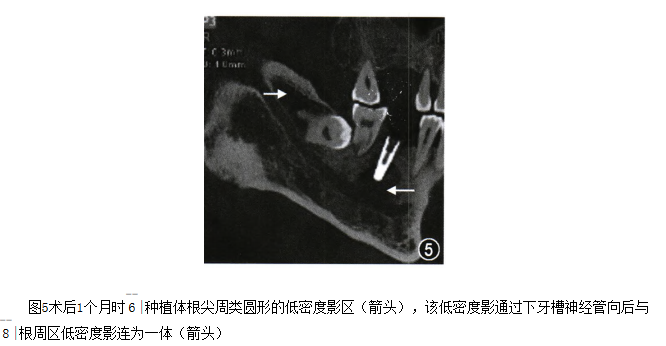

术后1个月就诊,述自戴义齿后种植牙区跳痛,近日疼痛加剧。

检查:体温:36℃,脉搏:80次/min,呼吸:20次/min,血压:120/80mmHg(1mmHg=1.33kPa),白细胞计数:5.8×109个/L。6——|种植义齿无临床动度,牙龈(-),叩痛(+)。锥形束CT矢状位片示:6——|种植体根尖周有一7mm×8mm类圆形的低密度影区,该低密度影通过下牙槽神经管向后与8I根周区低密度影连为一体,8——|冠周区同样有低密度影像区(如图5),种植体与邻牙周围骨组织密合无透射间隙。

图5.png